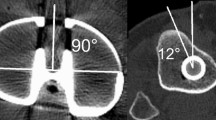

To identify the ML-axis and the med-1/3-axis, first the anatomical landmarks of the tibia had to be determined. This was done according to the techniques as described by Lawrie et al. [18] using ImageJ. For identifying the ML-axis, the tibial plateau center (TPC), the medial plateau center (MPC), and the lateral plateau center (LPC) were defined. To define the MPC, 15 points were placed along the cortical edge of the medial tibia, and the center of the circle best fitting these points was calculated as the MPC. Likewise, for defining the LPC, 15 points were placed on the edge of the lateral compartment of the tibia, and the center of the circle best fitting these points was calculated as the LPC. From these two points, the TPC was found by drawing a line through the MPC and LPC, extending this line to the medial and lateral edges of the tibia and defining the midpoint of this line as the TPC. The ML-axis as one rotational alignment was then simply a line starting at the TPC and perpendicular to the line connecting the MPC and LPC (Fig. 2a, b).

For identifying the med-1/3-axis as the other rotational alignment, first the medial third of the tibial tubercle and the center of the tibia in the second plane was selected. A line was drawn connecting the most lateral and the most medial aspects of the tibial tubercle, divided by three and the medial one-third selected. The center of the tibia in the second plane was determined as the center of the circle best fitting 15 points placed on the cortex of the tibia (Fig. 2c, d).